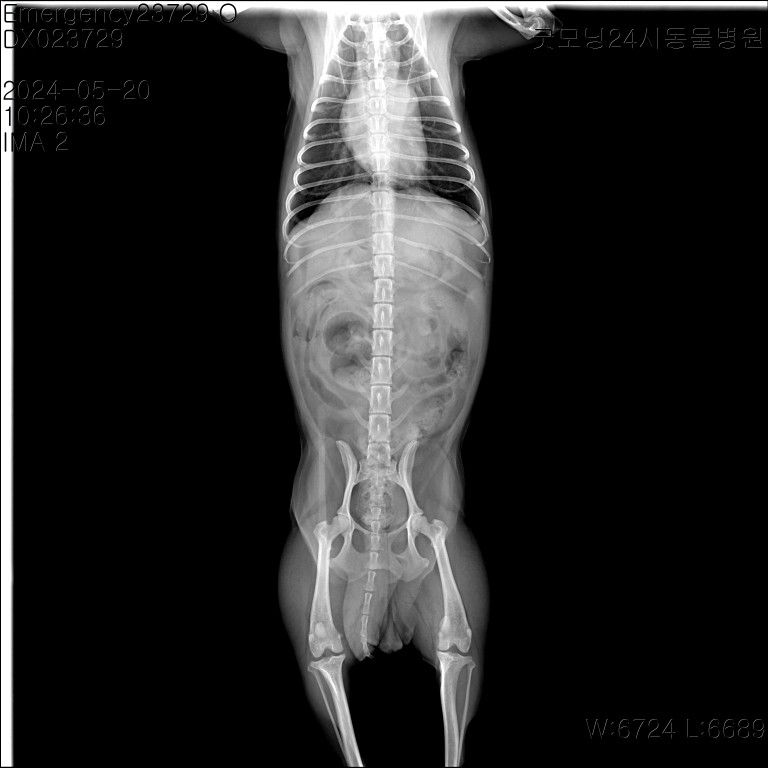

강아지 엑스레이 한 번만 더 봐주세요 부탁드립니다

어제 유선종양 한 토이푸들 견주입니다. 어제 수술 전 찍은 엑스레이인데 혹시 저 동그라미 친 곳이 유선종양일까요? 종양이 아니라면 뭘까요..? 그리고 엑스레이 상으로 전이소견은 안 보이는 거 맞죠..? 따로 또 문제 되보이는게 있을까요?

그리고 종양이 여러개인데 한 개만 조직검사를 의뢰했어요 양성의 결과가 나와도 여러개의 종양 중 한 개만 조직검사를 의뢰했던 거니까 추적관찰은 해주는게 좋은가요..?

• 이론적인 부분으로는 종괴나 미네랄침착, 혹은 장중첩까지 매우 다양하게 해석할 수 있습니다. 다만, 단순 방사선 사진만으로 단순히 high opacity 라고 해당 병변을 종양이라고 할 수 없으며, 진료 간 촉진 등 여러가지 요소가 다 포함되어야 합니다. 조직검사를 통해 양성/악성 여부가 확인되며, 양성이라도 향후 추적관찰이 필요한지에 대한 절제한 조직의 병변의 변형/화생정도를 평가하기 때문에 역시 검사 후 나타나는 결과를 들으셔야합니다. 걱정이 많으시겠으나, 부정확한 정보로 오히려 혼란스려움을 드리기 보단, 진료보신 동물병원 선생님의 진단과 처치를 기다려 주시길 바랍니다.

• 똥입니다. 표기한 부위의 밀도가 무기질 밀도인데 복배상에서 재현성이 없기에 실존하는 구물로 볼 수없고, 해당 부위에 분변들이 여럿 있기 때문에 겹침현상에 의한 허상으로 판단됩니다.